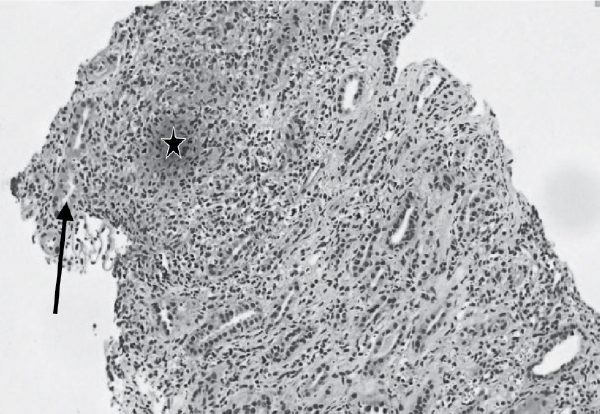

to Nephrologist for opinion due to deranged KFT. The patient underwent renal biopsy, which showed features of granulomatous interstitial nephritis. Focal glomerulosclerosis and mild interstitial fibrosis with tubular atrophy (15%) seen along with

evidence of tubular injury (Figs. 3 and 4). So, a final diagnosis of sarcoidosis with both lung and renal involvement was made.

Figure

4. Renal biopsy: Granulomatous interstitial nephritis (tubular injury- arrow, ill-defined granuloma- star).